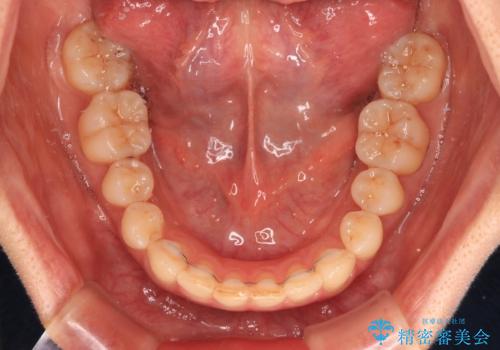

僅か1年間できれいに歯列を整えることができ、患者様には大変満足していただきました。